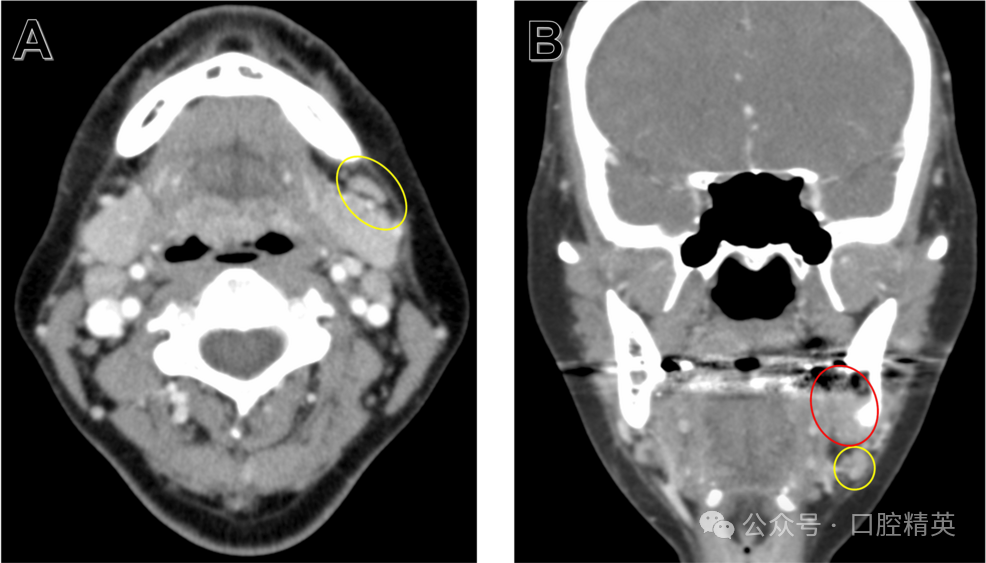

进一步CT检查显示,36、37及38周围舌侧骨皮质存在不规则吸收(图2)。

图2 初诊CT影像

36-38区域轴位(A)、冠状位(B)、矢状位(C)影像可见舌侧骨皮质不规则吸收(黄圈示骨皮质破坏关键表现)。

CT进一步证实舌侧骨皮质吸收并侵犯下颌管(图5)。

图5 38拔牙后CT(硬组织模式)

(A)、冠状位(B)、矢状位(C)影像可见舌侧骨皮质不规则破坏性吸收并侵犯下颌管(黄圈示较术前舌侧骨皮质破坏进展)。